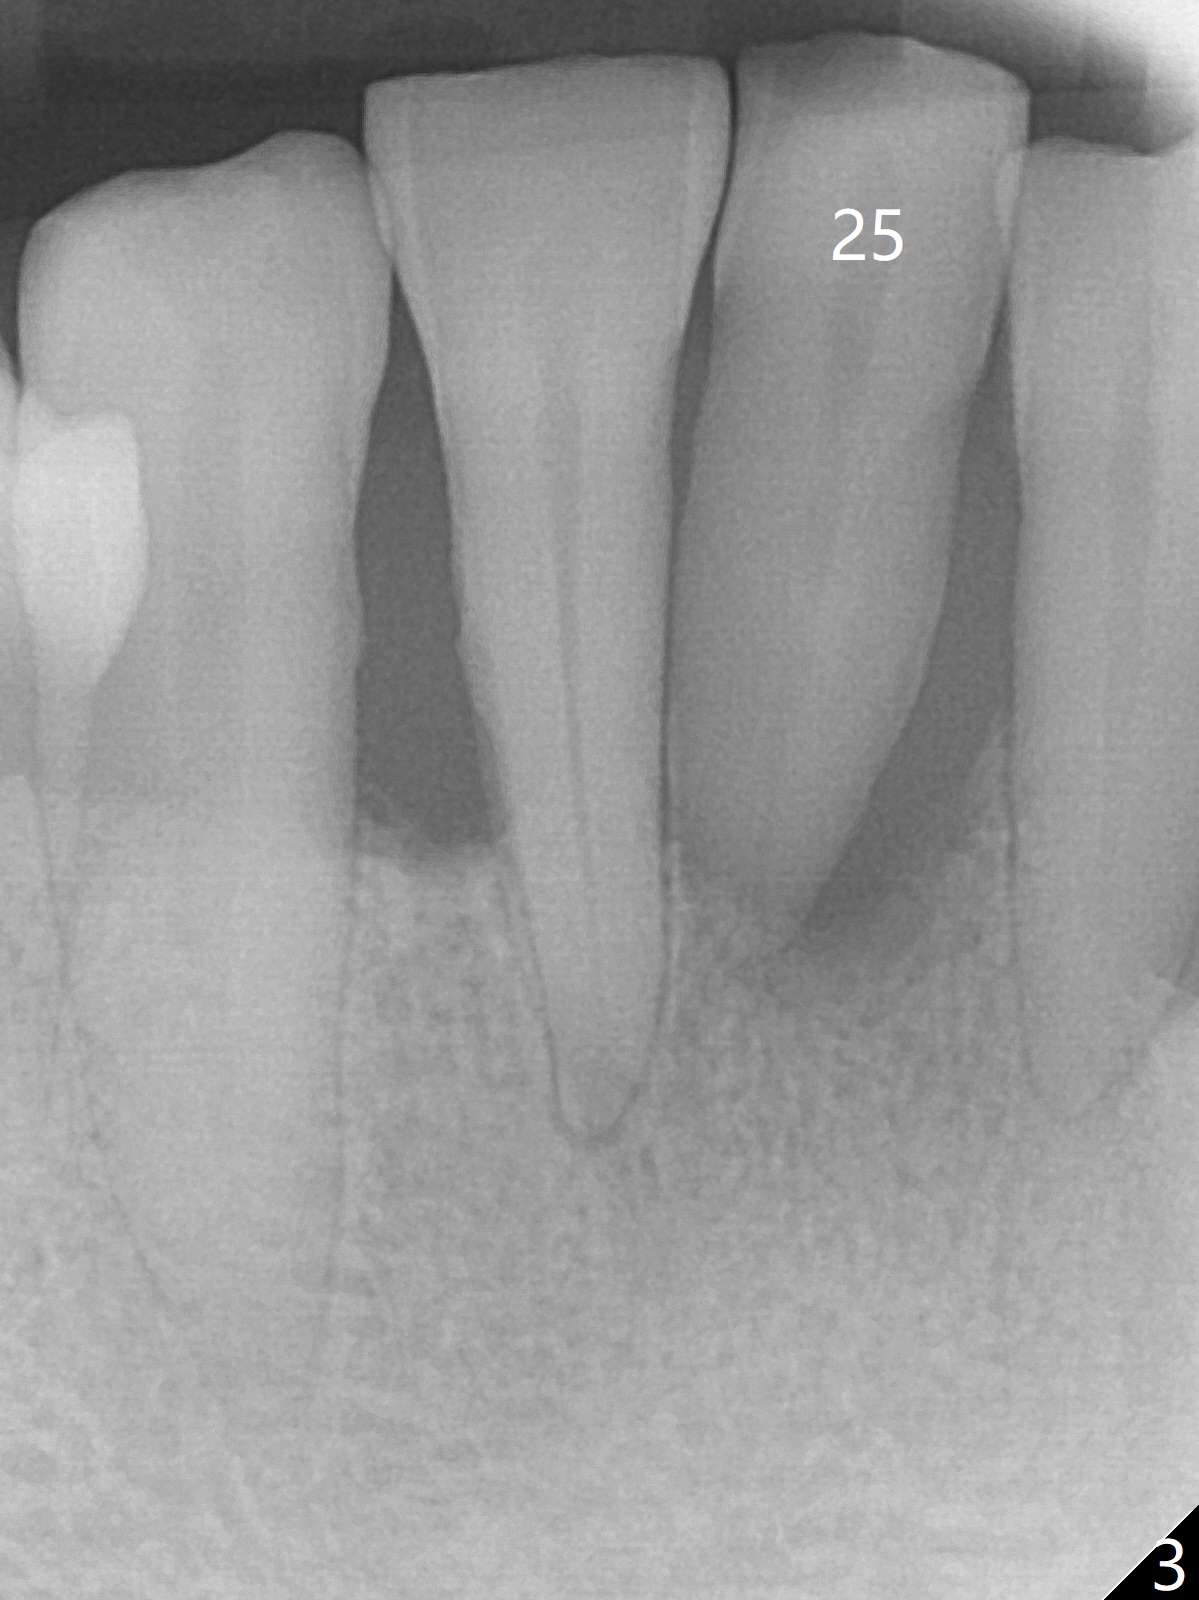

There is gingival inflammation at #25 buccally (Fig.1) and lingually (Fig.2). The bone loss is severe (Fig.3). Soft and hard tissue heights are 5 mm (cuff will be 4 mm) and 10 mm (implant will be 12 mm with 2 mm outside the native bone, Fig.4). The apex of the affected tooth appears deviated distal (Fig.5 *). The initial osteotomy happens to follow the long axis of the socket (Fig.6); to establish a correct trajectory, a new osteotomy should be made at the site labeled as a red line. In fact it is executed as planned (Fig.7). Because of the narrow flat ridge buccolingually, a 2.5x12(4) mm 1-piece implant is placed with >40 Ncm (Fig.8). With deeper placement of the implant, Vanilla graft is placed in 2 steps (Fig.9,10). The patient will return 2.5 months for extraction and implant of the fused teeth #22 and 23. No implant threads are exposed 10 months postop (Fig.11). CT taken 11 months postop shows that the 2.5 mm implant is in the middle of the bone (Fig.12) or 2 years post cementation (Fig.13).